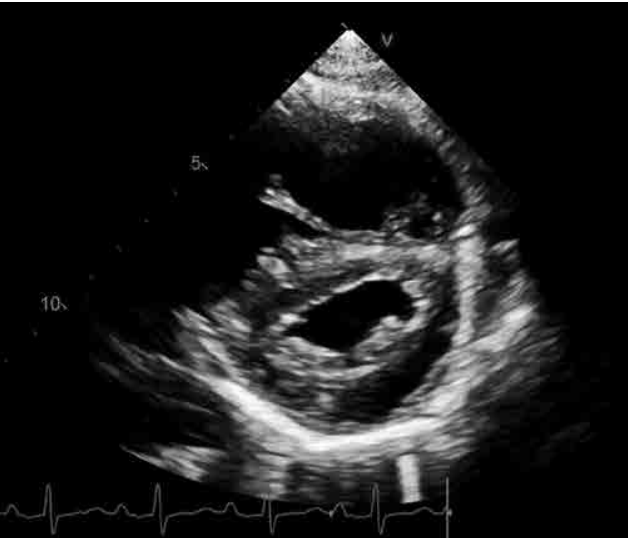

Imagem: arquivo pessoal.

O achado exibido na imagem acima e sua correlação clínica são